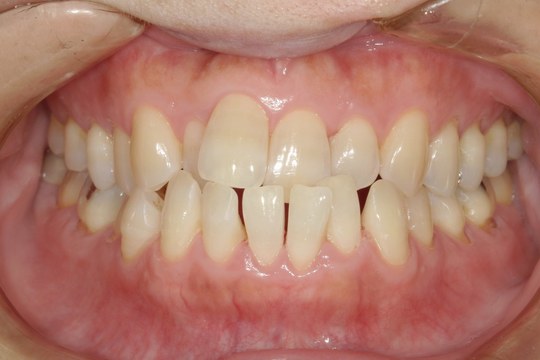

M.I. 40代女性

上下の前歯をキレイに並べたい、中心がズレている、という主訴でご来院。上下前歯の叢生を治し、正中を合わせました。

治療の期間:R3. 4/13〜R5. 8/30

治療の価格:88万円